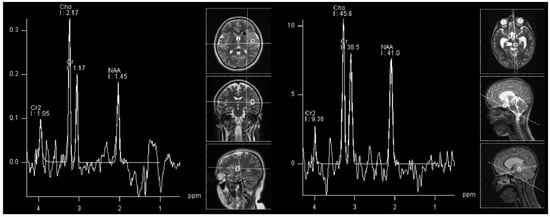

- Donia, M.; Abougabal, A.; Zakaria, Y.; Farhoud, A. Role of proton magnetic resonance spectroscopy in diagnosis of pilocytic astrocytoma in children. Alex. J. Med. 2012, 48, 131–137. [Google Scholar] [CrossRef]

- Porto, L.; Kieslich, M.; Franz, K.; Lehrnbecher, T.; Zanella, F.; Pilatus, U.; Hattingen, E. MR spectroscopy differentiation between high and low grade astrocytomas: A comparison between paediatric and adult tumours. Eur. J. Paediatr. Neurol. EJPN Off. J. Eur. Paediatr. Neurol. Soc. 2010, 15, 214–221. [Google Scholar] [CrossRef]

- Hasan, A.M.; Hasan, A.; Megally, H.; Khallaf, M.; Haseib, A. The combined role of MR spectroscopy and perfusion imaging in preoperative differentiation between high- and low-grade gliomas. Egypt. J. Radiol. Nucl. Med. 2019, 50, 72. [Google Scholar] [CrossRef]

- Shakir, T.; Fengli, L.; Chenguang, G.; Chen, N.; Zhang, M.; Shaohui, M. 1H-MR spectroscopy in grading of cerebral glioma: A new view point, MRS image quality assessment. Acta Radiol. Open 2022, 11, 205846012210770. [Google Scholar] [CrossRef]

- Toyooka, M.; Kimura, H.; Uematsu, H.; Kawamura, Y.; Takeuchi, H.; Itoh, H. Tissue characterization of glioma by proton magnetic resonance spectroscopy and perfusion-weighted magnetic resonance imaging: Glioma grading and histological correlation. Clin. Imaging 2008, 32, 251–258. [Google Scholar] [CrossRef]

- Öz, G.; Alger, J.; Barker, P.; Bartha, R.; Bizzi, A.; Boesch, C.; Bolan, P.; Brindle, K.; Cudalbu, C.; Dincer, A.; et al. Clinical Proton MR Spectroscopy in Central Nervous System Disorders. Radiology 2014, 270, 658–679. [Google Scholar] [CrossRef] [PubMed]